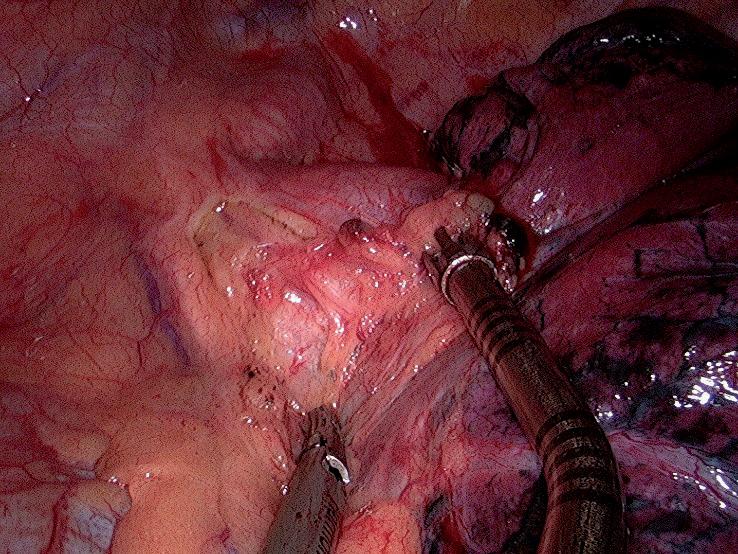

obr. 7.7 Průběh nervus laryngeus recurrens dexter, jež po odstupu z nervus vagus dexter zepředu dozadu obtáčí arteria subclavia dextra, pokračuje vzestupně a přiklání se postupně k průdušnici. Nebezpečí poranění tohoto nervu je u lymfadenektomie uzlin stanice 2R. Zejména při vinutém průběhu tepny vlivem hypertenzních aterosklerotických změn, který ji anatomicky posouvá nečekaně distálně. Na obrázku je preparační odsávačkou a prstenco vou cévní svorkou zachycena masa paratracheálních uzlin